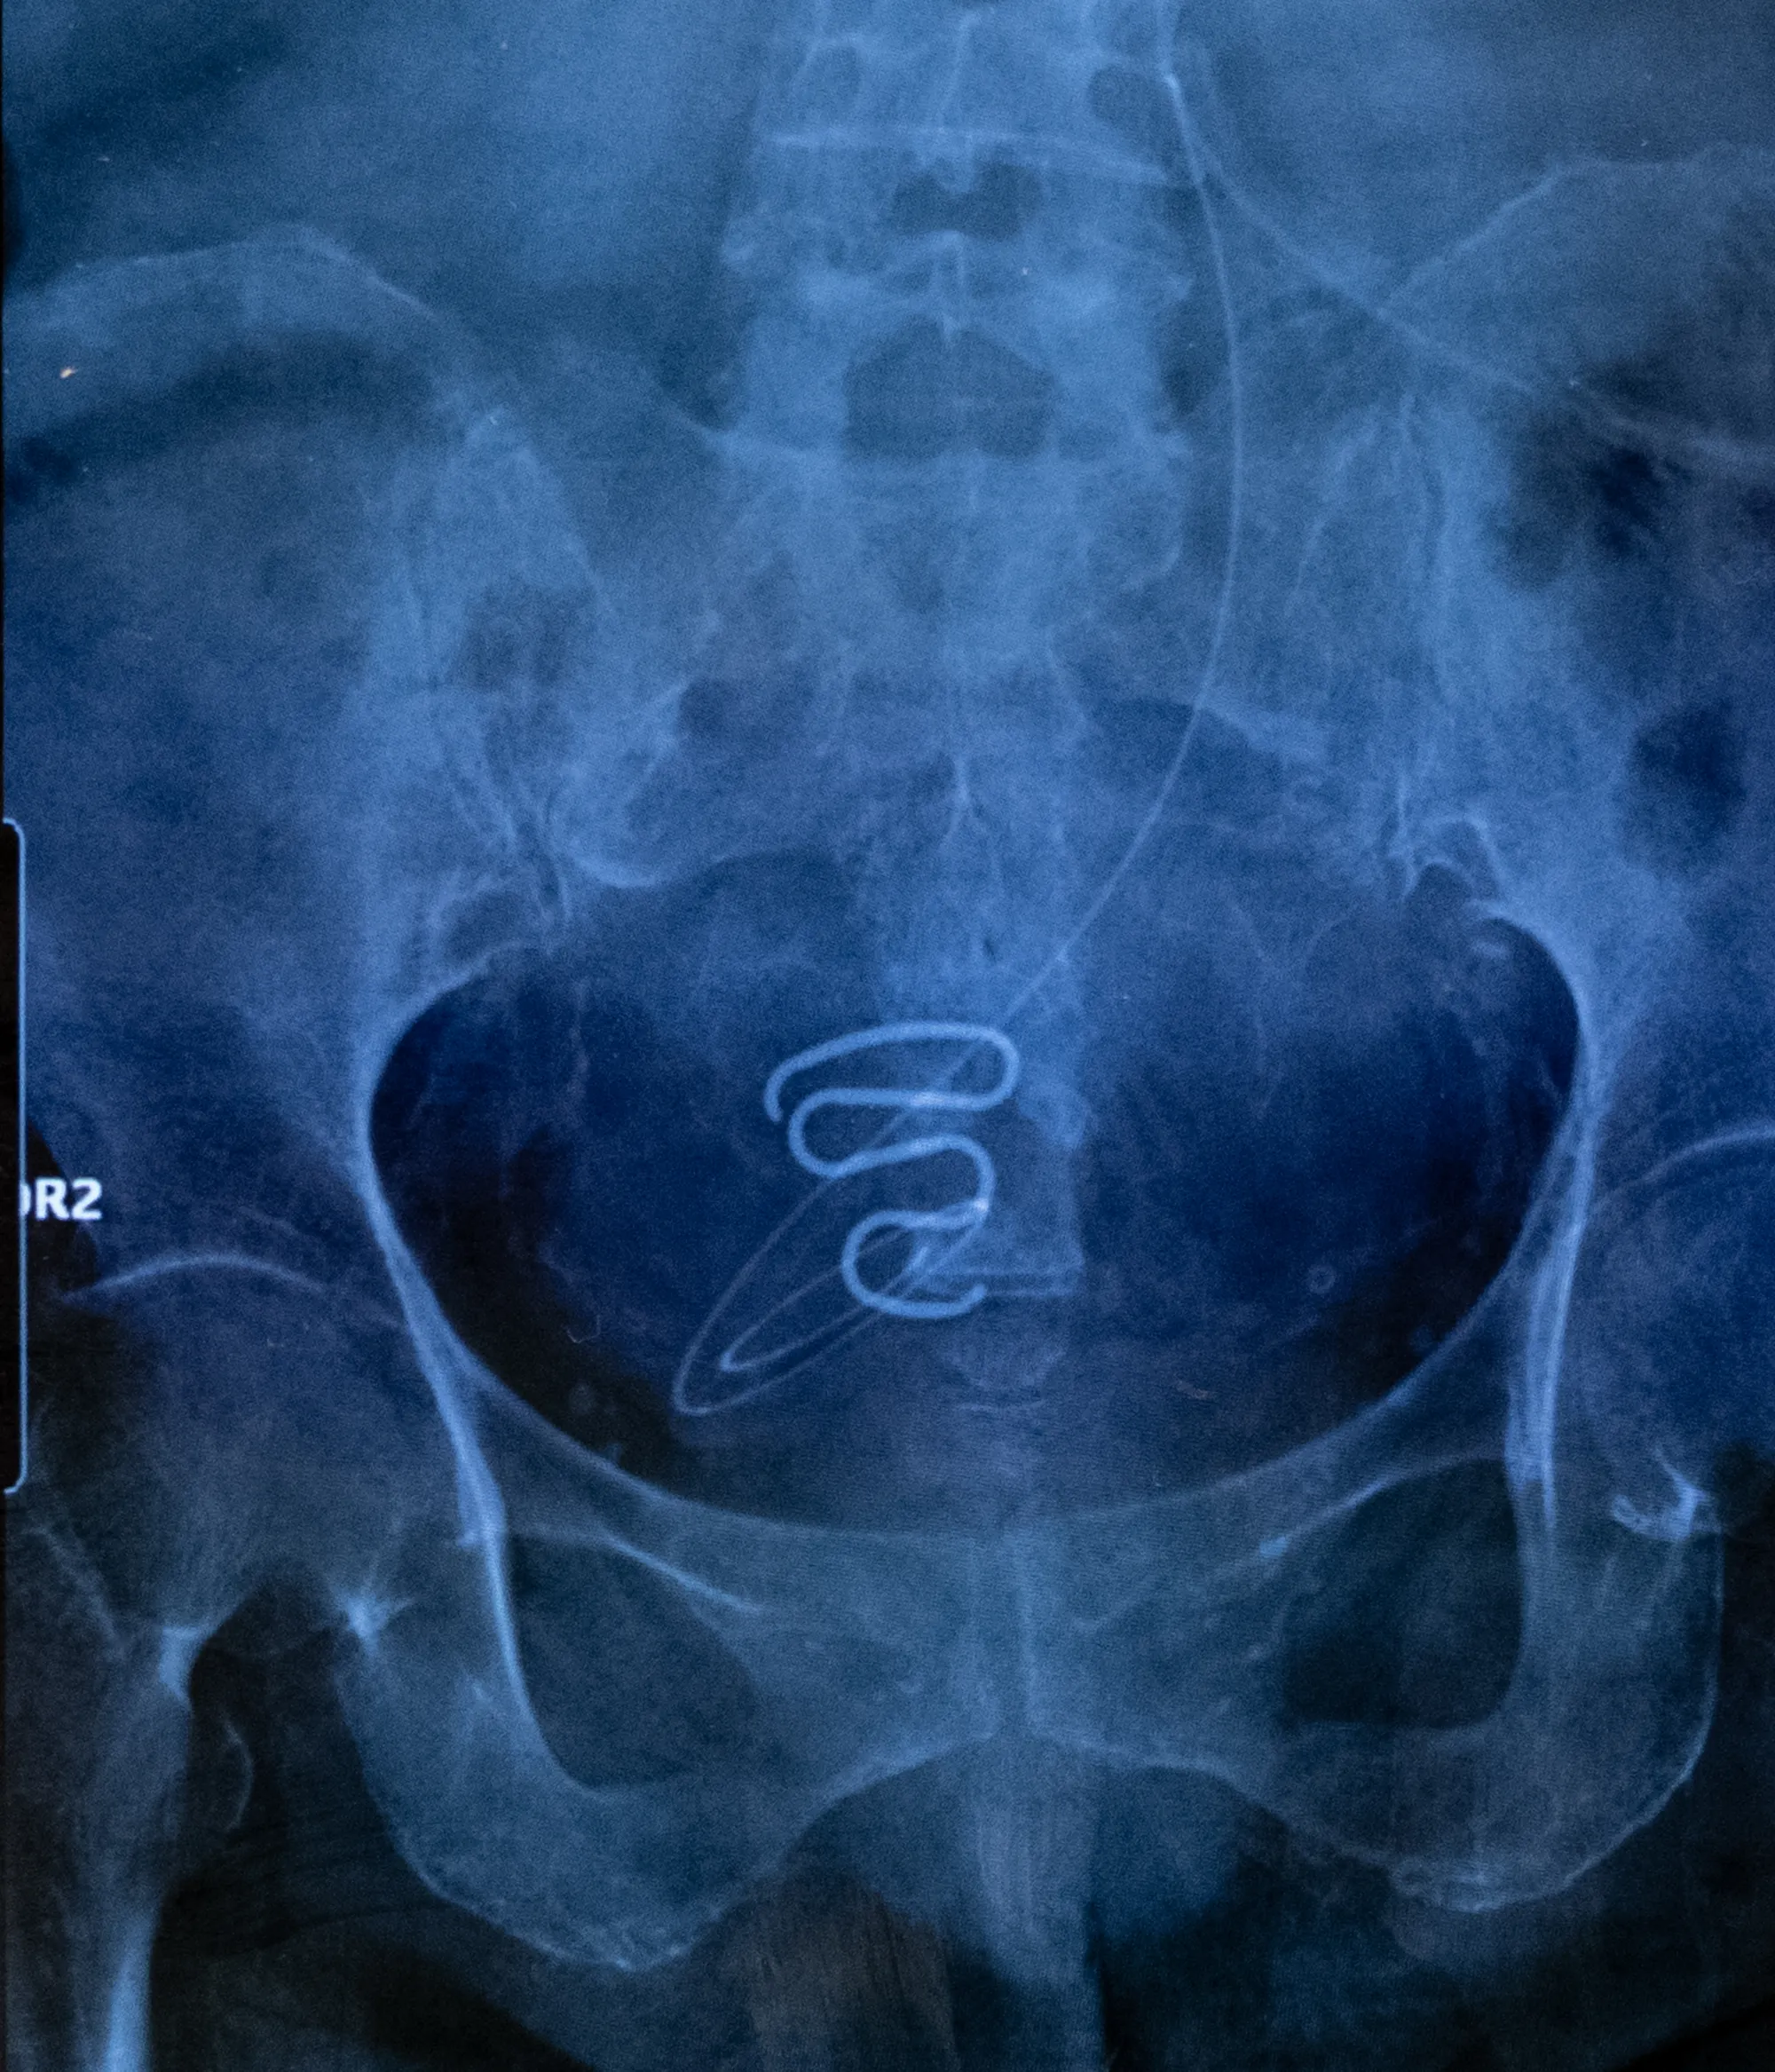

Congratulations to Juliette Pavy for being awarded the prestigious title of the Photographer of the Year 2024 for her series Spiralkampagnen: Forced Contraception and Unintended Sterilisation of Greenlandic Women by Juliette Pavy.

Winner: Juliette Pavy (France) for her series Spiralkampagnen: Forced Contraception and Unintended Sterilisation of Greenlandic Women